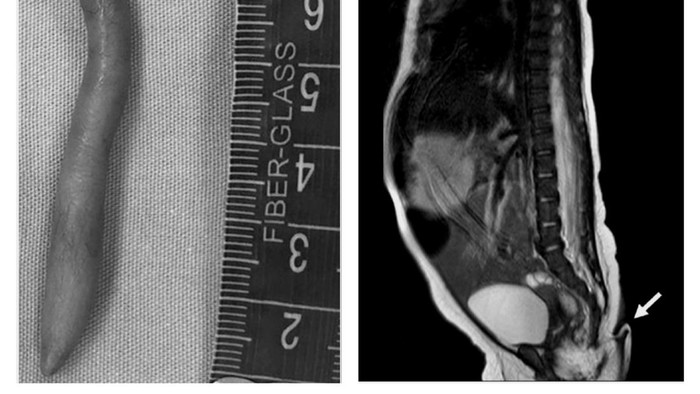

Pada saat bayi perempuan itu lahir, dokter melihat ada ekor yang lembut sepanjang 5,7 cm di bokongnya yang tertutup kulit dan rambut halus, serta memiliki ujung yang runcing. Pun, buntutnya juga mencuat di ujung tulang ekornya.

“Strukturnya lembut, tertutup kulit, dan rambut halus, dapat digerakkan secara pasif tanpa rasa sakit, tetapi tidak menunjukkan gerakan spontan,” tulis para dokter, dikutip dari Daily Mail.

Hasil pemindaian mengungkapkan ekornya bukan akibat dari masalah tulang belakang, seperti disrafisme spinal atau kondisi saat tulang belakang tidak terbentuk dengan benar hingga menyebabkan pertumbuhan daging seperti ekor di bagian bawah tulang belakang.